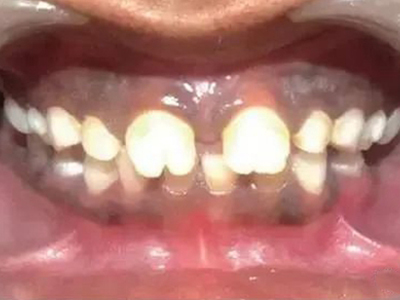

先天性梅毒牙主要表现为半月形切牙以及桑葚状磨牙,具体表现如下:

2、桑葚状磨牙:第一恒磨牙(牙合)面缩小,牙尖萎缩,呈发育不良的结节状压挤在一起,釉质呈小颗粒状或坑窝状凹陷,似桑葚样。牙冠短小,牙尖向中央聚拢而颈部周径大,牙齿可呈暗褐色。